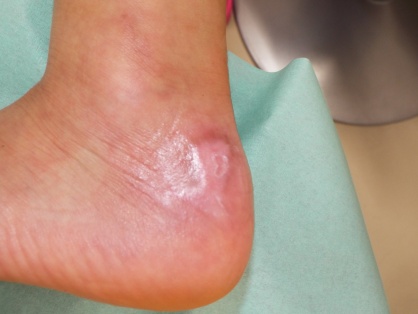

上皮化後1.5カ月目です。

時期的にキズアト(瘢痕)が一番目立ってくる頃ですが、予想された経過より良い状態が保てています。

上皮化後6か月目です。

キズアトの盛り上がり・赤みも改善しつつあり、ツッパリなどの運動制限もありません。